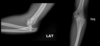

116

¿Qué signo es este y qué indica?

Pluma de ave: desgarro muscular grado 1 (hiperseñal)

121

La luxación de codo se asocia a: | Puede condicionar:

* Fractura de coronoides * Fractura de olécranon * Lesión ligamentaria | Compromiso neural